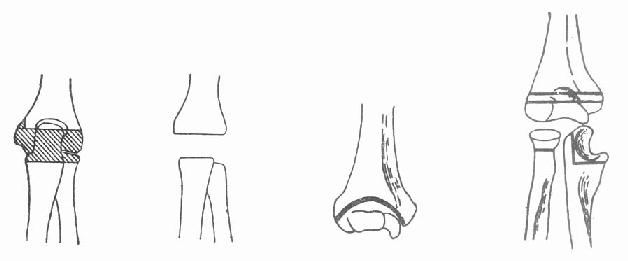

对早期单纯骨结核应及时作病灶清除,植骨充填空腔。如为滑膜型,则作滑膜切除,伤愈后及时活动以保护关节的活动度。如为全关节结核,宜作关节切除术(图3-228),以保持关节的活动度。

(1)肘关节切除范围(2)肘关节除后上、下

(3)肱骨下端分叉状(4)尺骨上端L形切除骨端的距离(3~4厘米)

图3-228 肘关节结核病灶清除和关节切除术